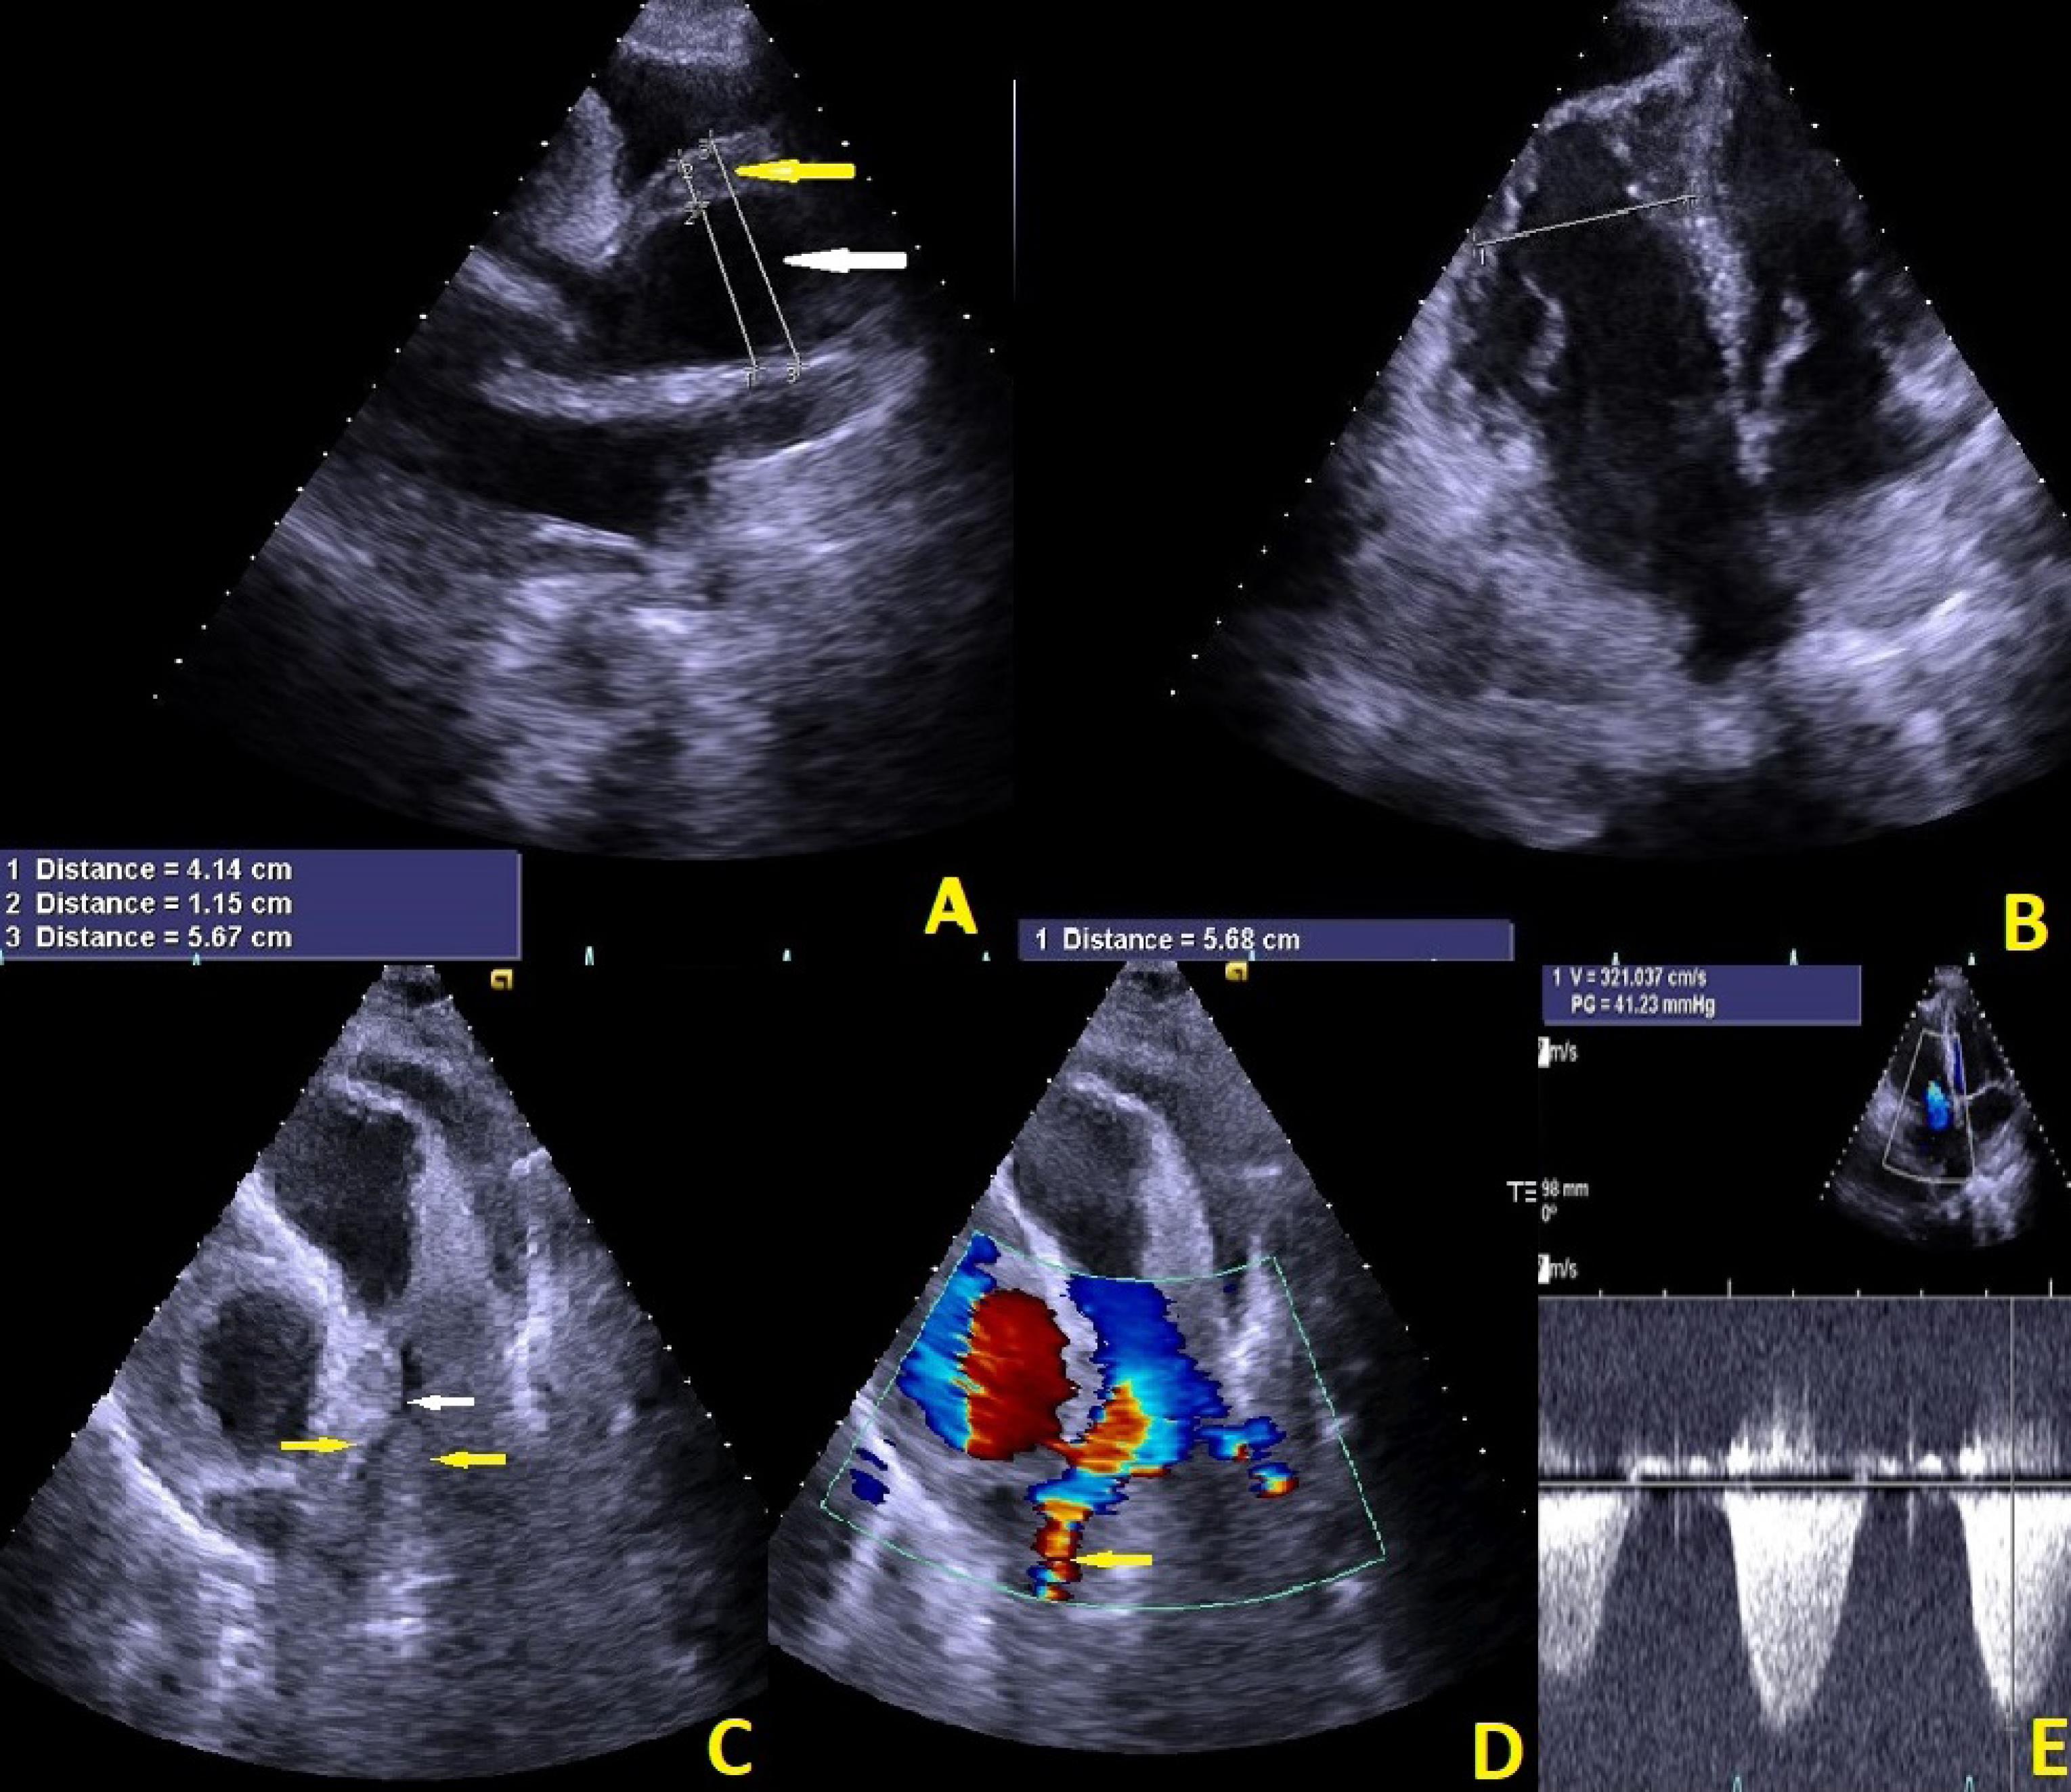

Tricuspid valve was not stenotic with moderate regurgitation and TRG of 40 mmHg. Pulmonary artery systolic pressure (PASP) based on estimated RA pressure of 15 mmHg was 25 mmHg. Aortic valve was tricuspid with sclerotic changes and mild stenosis and moderate insufficiency. Aortic wall was thickened from STJ, extended to distal part of ascending aorta indicative for intramural hematoma (IMH) (proximal part; (IMH) thickness: 11mm, true lumen: 41mm, total diameter: 56mm) (distal part; false lumen: 19mm, true lumen: 45mm, total diameters: 63mm). No coarctation of aorta was seen. Mild pericardial effusion (8mm) was seen (Figure 2, Movie 1 and Movie 2). After these evaluations aortic dissection was the suspected diagnosis therefore antiplatelet and anticoagulant therapy were discontinued.

Figure 2.

Transthoracic echocardiographic image in parasternal long axis view demonstrates thickened aortic wall from STJ, extended to the distal part of ascending aorta (yellow arrow) indicative of intramural hematoma (A). Markedly dilated right ventricle in four-chamber view (B) Large hematoma around right pulmonary artery (yellow arrows) and right pulmonary artery narrowing (white arrow) (C). Right pulmonary artery narrowing inducing systolic turbulency (yellow arrow) and gradient of 30 mmHg (D and E)

Movie Clip (1): Indicates the Figure number (2). Red arrow shows long axis view and aortic intramural hematoma.

Movie Clip (2): Indicates the Figure number (2). Yellow arrow shows narrowing and white arrow shows systolic turbulent flow of right pulmonary artery because of large hematoma around it.